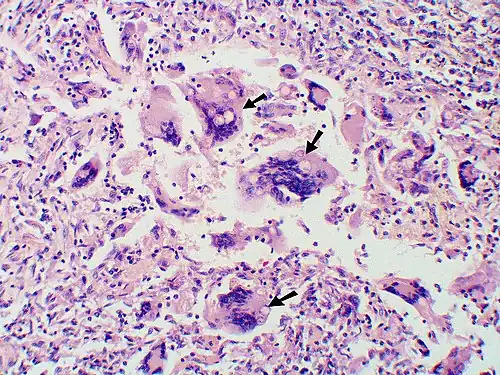

Large, broadly-based budding yeast cells characteristic of Blastomyces dermatitidis in a GMS-stained biopsy section from a human leg.

Once suspected, the diagnosis of blastomycosis can usually be confirmed by demonstration of the characteristic broad-based budding organisms in sputum or tissues by KOH prep, cytology, or histology.[27] Tissue biopsy of the skin or other organs may be required to diagnose extra-pulmonary disease. Blastomycosis is histologically associated with granulomatous nodules.